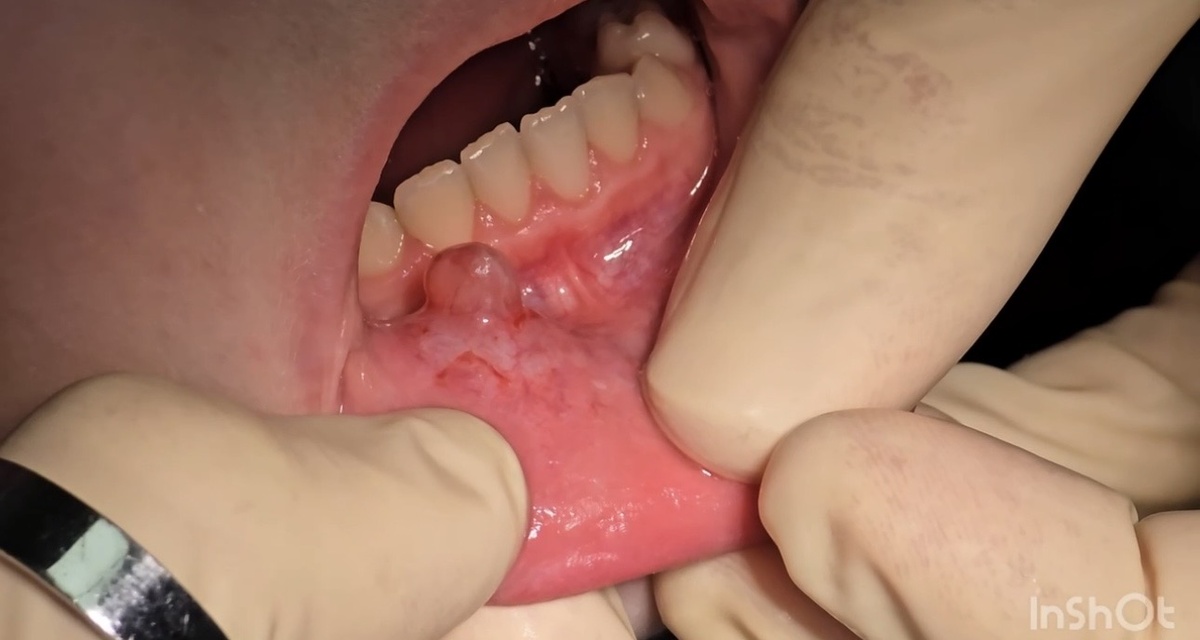

Сегодня поделимся интересным клиническим случаем - удалением ретенционной кисты на нижней губе. Ретенционная киста — это доброкачественное образование, возникающее из-за закупорки протока мелких слюнных желез, чаще всего на слизистой нижней губы. Такое новообразование формируется из-за скопления в протоке вязкого секрета, который не может выйти наружу из-за травмы, воспаления или других причин. Представляет собой плотный или мягкий шарик, покрытый тонкой оболочкой, который может менять цвет от ярко-розового до синюшного, и размером обычно до 2 см. Причинами возникновения ретенционной кисты становятся частые травмы (прикусывание, ожоги, пирсинг), воспалительные процессы и нарушение оттока слюнного секрета. Киста долгое время может не доставлять дискомфорта, но при росте вызывает неприятные ощущения, затрудняет речь или прием пищи, а без лечения возможно воспаление и нагноение. В нашей клинике мы успешно ведём такие случаи и проводим хирургическое удаление ретенционных кист с применением

Ретенционная киста — это доброкачественное образование, возникающее из-за закупорки протока мелких слюнных желез, чаще всего на слизистой нижней губы. Такое новообразование формируется из-за скопления в протоке вязкого секрета, который не может выйти наружу из-за травмы, воспаления или других причин. Представляет собой плотный или мягкий шарик, покрытый тонкой оболочкой, который может менять цвет от ярко-розового до синюшного, и размером обычно до 2 см.

Причинами возникновения ретенционной кисты становятся частые травмы (прикусывание, ожоги, пирсинг), воспалительные процессы и нарушение оттока слюнного секрета. Киста долгое время может не доставлять дискомфорта, но при росте вызывает неприятные ощущения, затрудняет речь или прием пищи, а без лечения возможно воспаление и нагноение.

На видео как раз происходит удаление ретенционной кисты с нижней губы, которое поможет лучше понять процесс и его особенности.